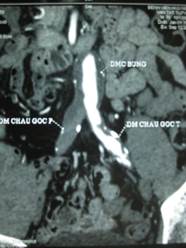

Ảnh: BN 5 với tắc ĐM chậu P, hẹp ĐM chậu T

Hẹp tắc ĐM chậu chung, chậu ngoài P, Hẹp ĐM chậu ngoài T, tắc ĐM đùi nông T |

Nong ĐM chậu ngoài T, phẫu thuật bắc cầu đùi-đùi T-P (mạch nhân tạo) |